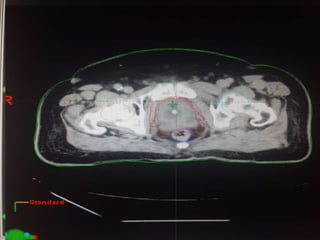

RTOG GU Consensus on pelvic LN CTV volumes:

 Commence contouring the pelvic CTV LN volumes at the L5/ S1

interspace (the level of the distal common iliac and proximal

presacral lymph nodes).

 Place a 7-mm margin around the iliac vessels connecting the

external and internal iliac contours on each slice, carving out

bowel, bladder, and bone.

 Contour presacral lymph nodes from S1 through S3, posterior

border being the anterior sacrum, and anterior border

approximately 10 mm anterior to the anterior sacral bone

carving out bowel, bladder, and bone.

 Stop external iliac CTV lymph node contours at the top of the

femoral heads (bony landmark for the inguinal ligament).

 Stop contours of the obturator CTV lymph nodes at the top of

the symphysis pubis.

Our unit decide to treat:

 Prostate + S.V & prophylactic Pelvic LNs in

phase1

 Prostate + S.V phase 2

 Delineation of our unit illustrated in the

following slides:

RTOG GU Consensuson pelvic LN CTV volumes:  Commence contouring the pelvic CTV LN volumes at the L5/ S1 interspace (the level of the distal common iliac and proximal presacral lymph nodes).  Place a 7-mm margin around the iliac vessels connecting the external and internal iliac contours on each slice, carving out bowel, bladder, and bone.  Contour presacral lymph nodes from S1 through S3, posterior border being the anterior sacrum, and anterior border approximately 10 mm anterior to the anterior sacral bone carving out bowel, bladder, and bone.  Stop external iliac CTV lymph node contours at the top of the femoral heads (bony landmark for the inguinal ligament).  Stop contours of the obturator CTV lymph nodes at the top of the symphysis pubis.

Our unit decideto treat:  Prostate + S.V & prophylactic Pelvic LNs in phase1  Prostate + S.V phase 2  Delineation of our unit illustrated in the following slides: